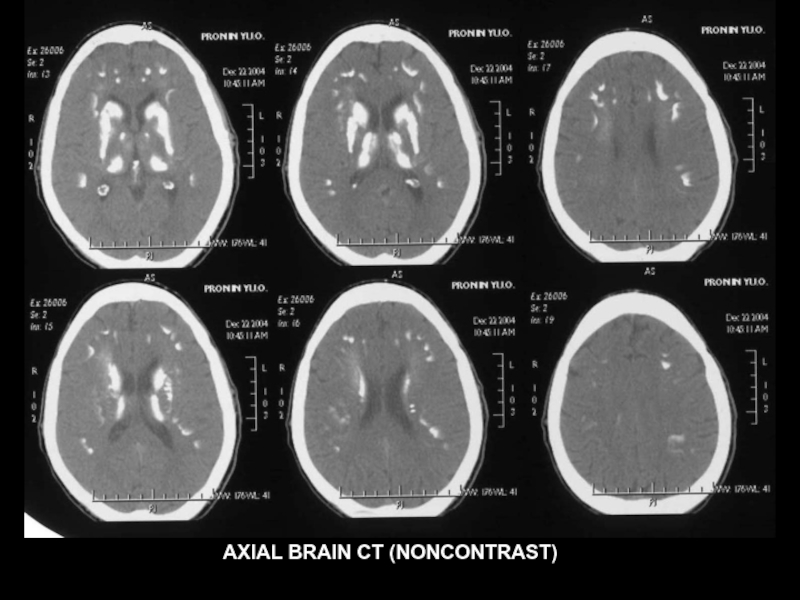

AXIAL BRAIN CT (NONCONTRAST)

Слайд 38

Слайд 39

Слайд 40

Слайд 41

Слайд 42